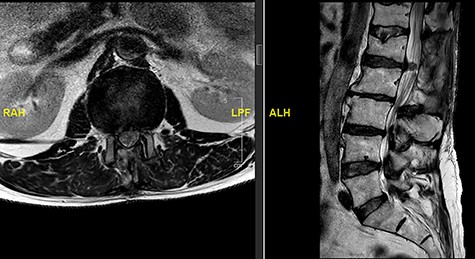

A 56-year-old male patient lumber decompression in a local neurosurgical centre for severe canal stenosis at L1/2 and L2/3 (Fig. 1) level after presenting with bilateral leg weakness and perianal numbness. Three months later he presented with recurrence of right leg pain radiating into the calf and worsening back pain as well as distal lower limbs weakness bilaterally with no sphincter problem. Following an magnetic resonance induction (MRI), which revealed a disc prolapse at L1/2 (Fig. 2), the patient was referred to our Centre. The images were reviewed by a consultant radiologist and as a possibly of intradural herniated disc disease was described. Intraoperatively no extradural disc prolapse was found, so midline durotomy was performed. Intradural disc herniation (IDH) was identified, which was communicating with the disc space through a midline defect in anterior dura (Fig. 3). This was removed extracted under the microscope. Post-operatively, he had a CSF leak needing re-suturing of dura. The patient did make a good post-operative recovery with no major sensory or motor deficits or sphincter disturbance.

MRI image revealing a recurrence of a disc prolapse, suspected to be an intradural disc at L1/2, confirmed intraoperatively.